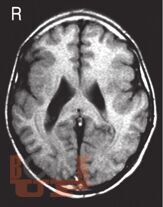

Чарльз Ньокиктьен известен как один из ведущих специалистов и основоположников нового научного направления - детской поведенческой неврологии - той области неврологии, которая изучает связь между проблемами в поведении и обучении и их неврологической основой. Впервые предлагаемый российскому читателю двухтомник обобщает современные данные неврологии и других нейронаук о развитии и отклонениях в развитии ребенка, а также неврологические и нейропсихологические методы их оценки.

Во II томе рассматриваются развитие памяти и внимания у детей и их расстройства, включая гиперактивное расстройство с дефицитом внимания, нарушения развития речи (дисфазия) и школьных навыков (дислексия, дисграфия, дискалькулия), аутистические расстройства, особые синдромы (поведенческие фенотипы), нейропсихиатрические нарушения, отставание и регресс в психомоторном развитии.